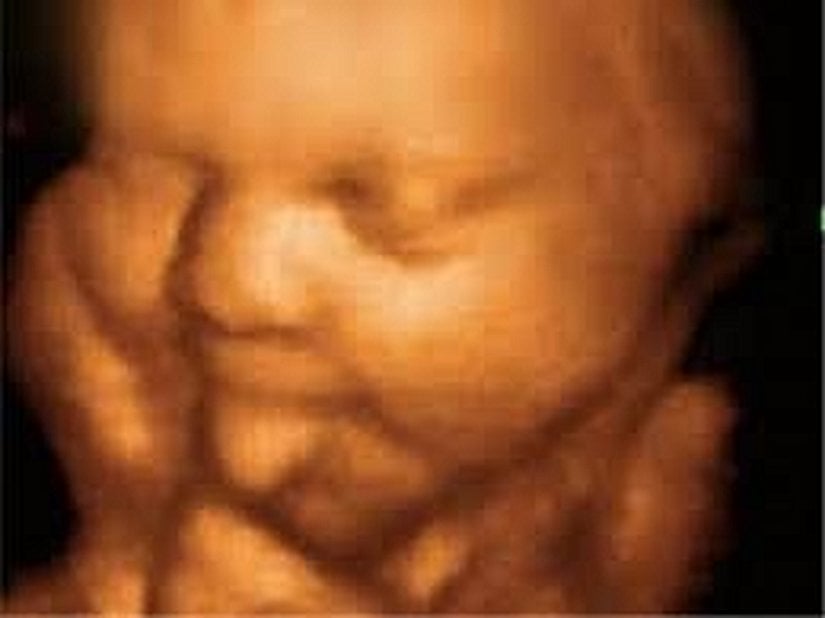

Ama giderek popülerleşen bir teknoloji sayesinde ebeveynler artık yavrularını çok daha net görebiliyorlar: 3D ve hatta 4D ultrason! Monako'daki Princes Grace Hastanesi'nde görev yapan Dr. Bernard Benoit, uzun yıllardır 3 boyutlu (ve hatta 4 boyutlu) ultrason görüntüleme teknikleri üzerinde çalışıyor ve çok başarılı sonuçlara da imza atmış vaziyette. Aşağıda, bunun bir örneğini görüyorsunuz.

Bu görüntüleme tekniği sayesinde, artık renkli ve çok daha net sonuçlara ulaşabiliyoruz. Bu görseller, bunun en net ispatlarından biri. Ana karnındaki ikizleri çok detaylı bir şekilde görüntülemek artık mümkün. Hem de o, uzaktan odaklanılmış bir kare. Aşağıdakiler, ne demek istediğimizi daha net anlatacaktır:

3D ultrasonlarda, birden fazla açıdan 2 boyutlu görüntüler çekiliyor ve sonrasında bilgisayar yardımıyla 3 boyutlu bir görsele dönüştürülüyor. Bu sayede bebeğinizin sadece bir kesidini değil, 3 boyutlu bir görüntüsünü elde etmeniz mümkün oluyor.

4D ultrasonlarda ise, 3D olan görüntüler zamana yayılmış bir şekilde kaydediliyor. Bu sayede bebeğin hareketlerini tıpkı bir video izler gibi görmeniz mümkün oluyor. Bu sayede bebeğin gözlerini açıp kapaması, gülümsemesi veya parmağını emmesi gibi olayları çok net bir şekilde görüntüleyebiliyorsunuz.

Bu yeni teknik, sadece ebeveynlerin yavrularını daha kısa sürede, daha net görmelerini sağlamayacak, aynı zamanda birçok hastalığın çok daha erkenden teşhisine katkı sağlayacak. Bu yeni yöntemler kullanılarak fetüsleri çok daha yakından görmek ve bu sayede doğuştan gelen bazı hastalıkları (tavşan dudaklılık, omurilik sorunları, vb.) çok daha erkenden tespit edebilmek mümkün oluyor. Şimdilik bu gelişmiş yöntemler, "sıradan doğum kontrollerinde" rutin olarak uygulanmıyor; ancak bir şüphe doğarsa uygulanabiliyor.